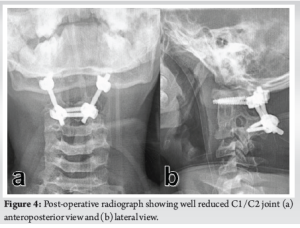

A 14-year-old boy presented to the spine clinic with progressive weakness of the bilateral upper limb, progressing to bilateral lower limb for the past 1.5 years following trivial trauma to the neck and with bowel and bladder incontinence for the past 1 year. At presentation, he was not able to stand without support, had increased tone (modified Ashworth grade 1) in bilateral upper and lower limbs, with functional motor power present and no sensory deficit in any of the dermatomes. On elicitation, both upper and lower limb reflexes were exaggerated. Exaggerated pectoralis reflex and presence of scapulohumeral reflex suggested a clinical diagnosis of supra-axial cervical myelopathy. On further evaluation, special signs such as Hoffman’s sign and grasp-release test were positive. Cervical spine radiograph showed atlantoaxial subluxation with decreased posterior atlanto-dens interval along with fusion of C2 and C3 vertebrae (Fig. 1). On magnetic resonance imaging cervical spine, thecal sac and spinal cord compression at the level of C1/C2 joint with no visible cerebrospinal fluid rim was noted (Fig. 2). 3D Computed tomography angiography (CTA) of the cervical spine showed an incomplete anterior and posterior arch of the atlas with well-corticated bony fragments within the posterior arch defect. Note of fenestration of VA on right side and high-riding VA was also made (Fig. 3). A final diagnosis of supra-axial extradural compressive cervical myelopathy due to congenital atlantoaxial subluxation with anomalous VA (Nurick Grade 5) was made. The patient was planned for C1-C2 reduction and posterior instrumented fusion using C1 lateral mass and C2 laminar screws under intraoperative neuromonitoring. The patient was positioned prone on Mayfield, and a longitudinal midline approach from C1 to C3 was carried out, elevating the paraspinal muscle subperiosteally from the midline. A congenital defect in the posterior arch of C1 was noted. First, the left side C1 lateral mass screw was put after identifying the entry point. On the right side, the aberrant VA was freed from the posterior arch of C1 and retracted, inferiorly exposing the lateral mass of C1 along with facets of C1-C2 joint, and C1 lateral mass screw was inserted. Further, laminar screws were placed bilaterally in C2. C1 was reduced over C2 using rod cantilever mechanism and by applying compression force bilaterally between the C1 lateral mass and the C2 laminar screws. Decompression was achieved by removing the remaining C1 posterior arch and corticated bony fragment from the midline. Harvested local bone autograft was placed in the C1-C2 joint on the left side and the prepared fusion bed posteriorly (Figs. 4 and 5).

Gait training was started, and post-operative neurological assessment showed normal tone in both upper and lower limbs at 6 weeks. At 6 months, the patient started walking with support and had complete recovery of bowel movements and partial recovery in bladder sensations. At final follow-up of 18 months, the patient is walking independently (Nurick Grade 2). The patient has returned to his routine daily activities with no motor deficit in bilateral upper and lower limbs (Fig. 6).